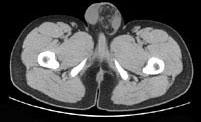

男,29岁,因左腹股沟突发痛性肿物3小时入院,左腹股沟皮下环处有一约4cm×5cm的肿物,触痛甚,质软,基底部有一细蒂,左阴囊发育小,睾丸缺如,CT检查如...

问题 男,29岁,因左腹股沟突发痛性肿物3小时入院,左腹股沟皮下环处有一约4cm×5cm的肿物,触痛甚,质软,基底部有一细蒂,左阴囊发育小,睾丸缺如,CT检查如图所示,下列说法错误的是 ( )

选项 A、腹股沟斜疝 B、左腹股沟区肿块为曲张的精索静脉 C、精索静脉曲张 D、腹股沟直疝 E、左睾丸下降不全

答案 D